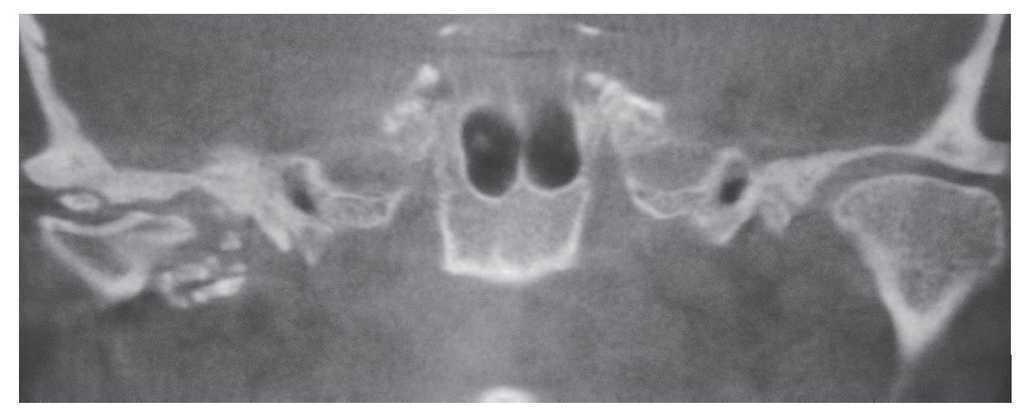

Para una valoración más detallada de las relaciones anatómicas y de las dimensiones de la calcificación se practicó una tomografía volumétrica digital dental. Se observaron múltiples calcificaciones de pequeño tamaño en la parte anterior y media del cóndilo articular (figs. 2 y 3). Se constató una calcificación de mayor tamaño directamente encima del cóndilo. Al mismo tiempo llama la atención un ensanchamiento marcado de la base craneal (fig. 4). Este hallazgo sugiere una posible etiología inflamatoria de las calcificaciones. En pacientes muy jóvenes hay que tener presente la posibilidad de una artritis reumatoide, si bien en el caso que nos ocupa la ausencia de sintomatología clínica iría en contra de este diagnóstico. La falta de síntomas es más bien una característica de la condromatosis sinovial. Esta enfermedad rara que se acompaña de la formación de encondromas aislados, los cuales se calcifican posteriormente, no suele provocar dolor en la articulación temporomandibular hasta fases avanzadas. Es posible observar encondromas libres en el espacio articular. En estos casos hay que hacer el diagnóstico diferencial con una osteocondrosis disecante (OCD).

Figura 3. Tomografía volumétrica digital dental: plano coronal.

Figura 4. Tomografía volumétrica digital dental: plano coronal. Obsérvese la anchura de la base craneal en comparación con el lado contralateral.